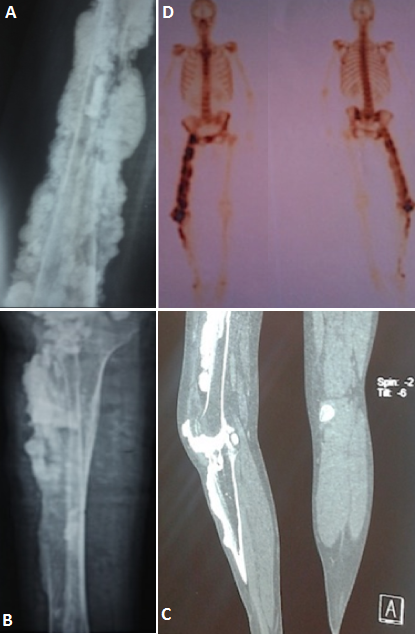

La mélorhéostose est une dysplasie osseuse sclérotique progressive. Son incidence est estimée à 0,9 par million d'habitants. C'est une maladie congénitale, décrite par A. Léri et L. Joanny en 1922. Elle reste méconnue du fait de sa rareté. Elle débute insidieusement dans l'enfance, et touche les os longs des membres inférieurs. Progressivement s'installe une raideur articulaire et une impotence fonctionnelle. La douleur, la raideur et les déformations articulaires constituent le profil évolutif de la maladie. Certaines hypothèses évoquent un émutation du gène du mésoderme et du gène LEMD3. Son diagnostic est posé sur les données caractéristiques des radiographies standard. L'histologie est inutile en cas de forme typique. Nous en rapportons un cas chez une patiente âgée de 44 ans, présentant depuis l'âge de 12 ans, des gonalgies droites mixtes et intermittentes, soulagées par traitements symptomatiques. L'évolution était marquée par la reprise de la même symptomatologie occasionnant progressivement une boiterie à la marche, et apparition d'une tuméfaction et incurvation de la cuisse du même côté. L'examen physique retrouvait; une attitude du membre inférieur droit en rotation externe et abduction, une tuméfaction de la cuisse et une raideur de la hanche et du genou droit. Le bilan biologique était normal. Les radiographies standard retrouvaient de multiples pacitéslongilignes en «coulées de bougie» s'étendant le long de la corticale fémorale et tibio-peronièredroite et ossifications des tissus mous para articulaire et osseux ( A et B), confirmées au scanner (C) et à la scintigraphie osseuse, fixant les zones d'ostéoformation (D). La patiente était mise sous antalgiques et bisphosphonates orale. Le diagnostic différentiel se pose avec l'ostéosarcome paraostéal, la myosite ossifiante, l'hématome calcifié ou une ossification des parties molles. Le traitement fait appel aux antalgiques, bisphosphonates, colchicine, vasodilatateurs, corticothérapie. La chirurgie en association avec une rééducation sont proposées pour limiter la maladie.